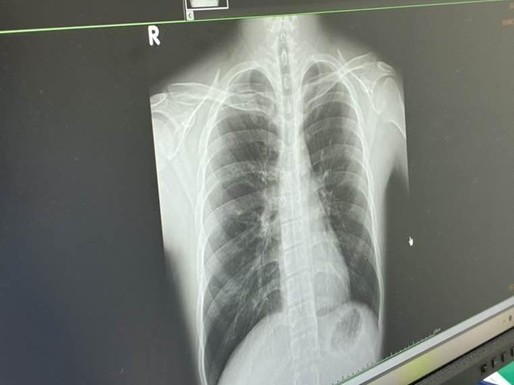

黴漿菌肺炎關鍵徵兆非咳嗽 護理師:胸悶、吸氣不順 要留意

華岡融媒體記者/陳奕瑋報導 近期黴漿菌肺炎病例大幅激增,不少患者在治療兩週甚至到一個月仍然咳嗽不止,最終經過醫師診斷,才確認是黴漿菌肺炎。馬偕醫院兒童病房護理師廖朱滿表示,黴漿菌肺炎的初期症狀與一般感冒極為相似,許多家長常以為孩子只是普通咳嗽而輕忽,尤其「胸悶、吸氣不順」這類看似 ...